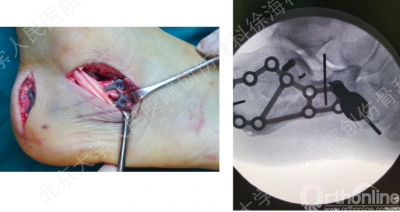

徐教授的方案

经跗骨窦小切口显露和复位距下关节

纠正跟骨结节骨块的内翻

经皮下隧道植入钢板

螺钉数量:三点固定原则

“三点”支撑固定